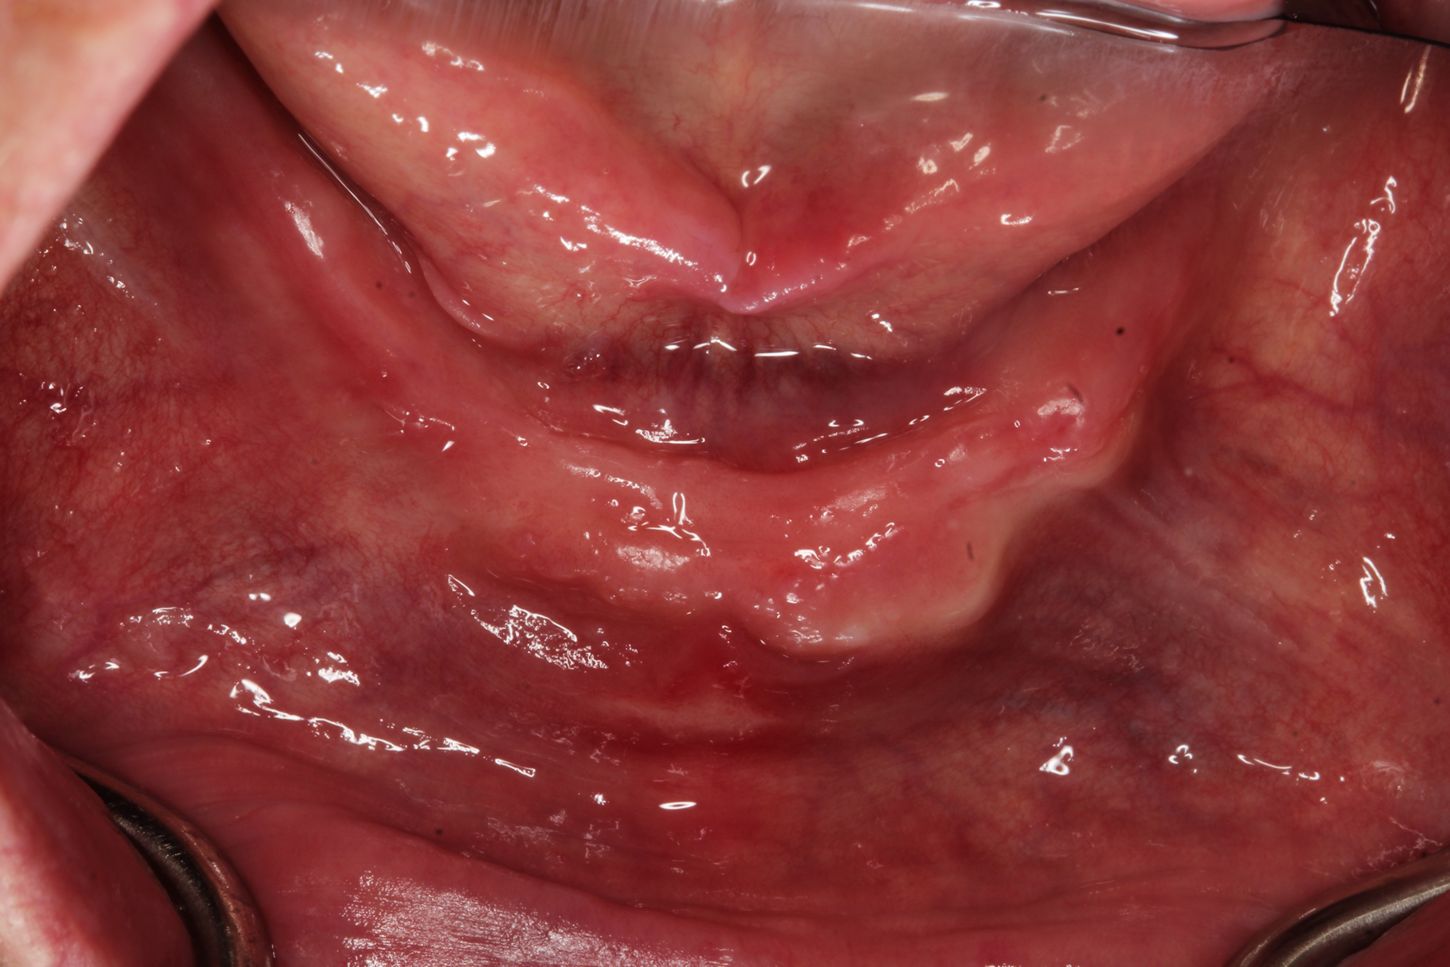

Since losing all his teeth due to periodontitis, this 72-year-old patient with a moderate/heavy smoking habit has been wearing a full-arch regular denture in the upper arch for 10 years and in the lower arch for two years. Although it is technically well produced, the lack of retention in his regular lower denture compromises his chewing functions. The bone is unevenly resorbed and the amount of fixed keratinized epithelium is limited compared to other areas (Figs. 1-4).